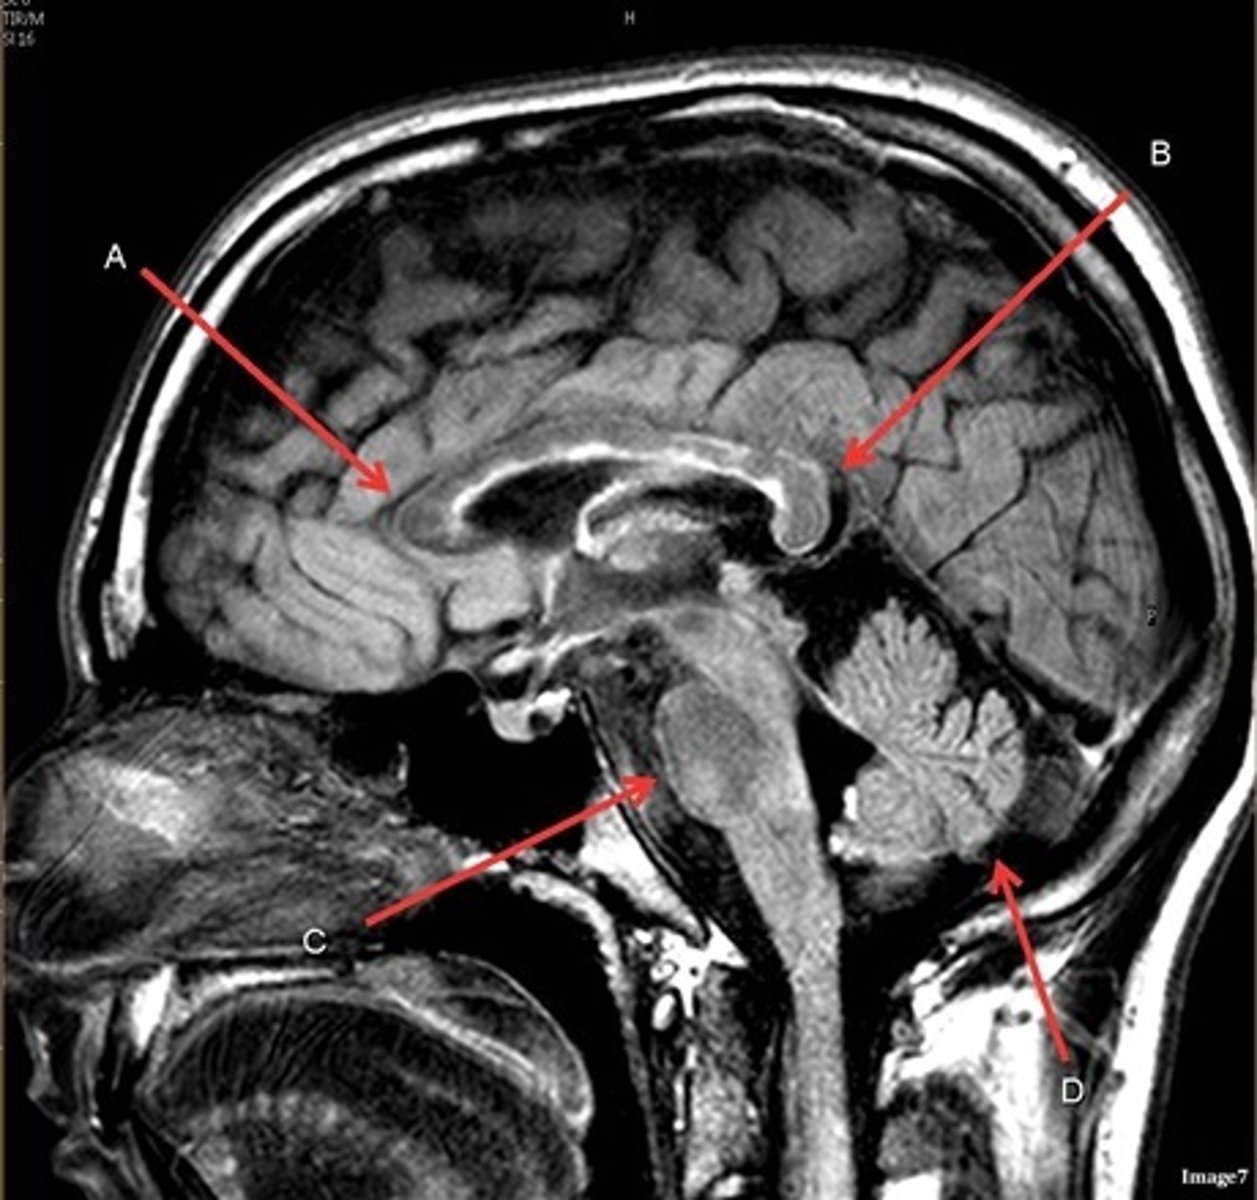

T1, sagittal

A- region

Genu of Corpus Callosum

B- region

Splenium of Corpus Callosum

C

pons

D

cerebellum